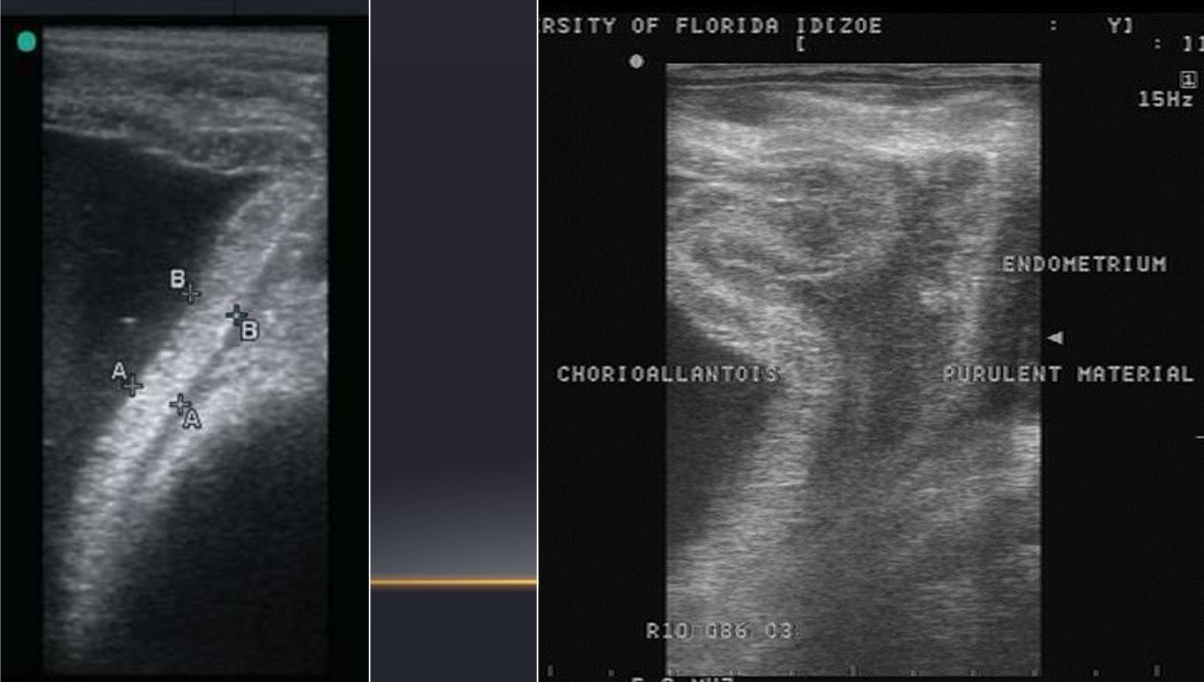

Quels sont les éléments observés à l’echographie lors du diagnostic des placentites (4)

• Séparation du placenta (Normalement, l’allanto-chorion est accolé parfaitement à l’endomètre. Sinon, du pus peut s’accumuler entre les deux)

• Matériel purulent dans la région interne du col de l’utérus

• Qualité du liquide allantoidien et amniotique (anormal: particules qui flottent, matériel heterogène)